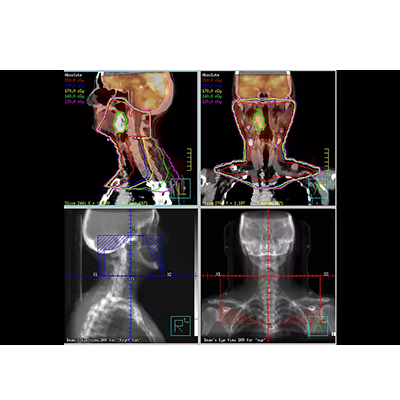

在您进行轮廓勾画以及使用多模图像配准进行 Pinnacle³ 整合治疗计划时,Syntegra能为您带来更强的信心。Syntegra 的多模配准软件能够缩短放射治疗周期,并取得更准确的诊断结果。

Syntegra 通过使用更快的交互信息、交叉相关和局部相关等算法来提高配准的准确性。您可以选择最适合自己临床应用的优化算法。

Syntegra 能够将生理学影像(如 PET 等)与解剖学影像(如 CT 或 MR)进行自动匹配,使临床医生无需手动调整匹配的影像。

作为飞利浦 Pinnacle³ 放射治疗计划系统的一部分,Syntegra 能够帮助您弥合诊断与治疗之间的鸿沟。例如,放射肿瘤科医生可以将 PET/CT 肿瘤轮廓输入 Pinnacle³ 治疗计划并对其进行回顾,并且可以使用放射科医师已经确定的影像和感兴趣区域。Syntegra 已被归为飞利浦 AcQSim³ CT 模拟软件的一个组成部分。